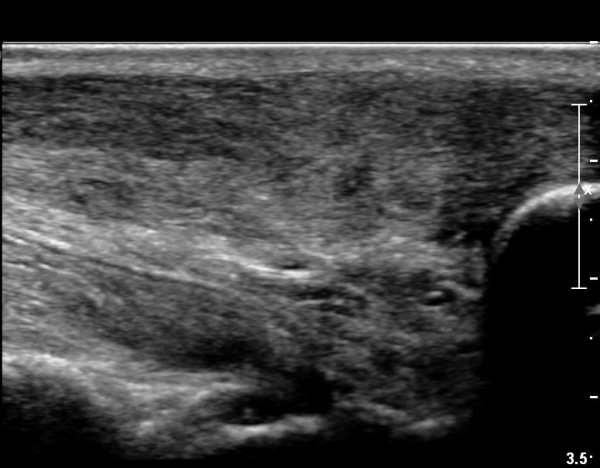

¾ÆÅ³·¹½º°Ç Àú¿¡ÄÚºÎÁ¾ÀÌ °¨¼ÒµÇ°í  ÆÄ¿­ºÎÀ§ Àú¿¡ÄÚ°¡ È£ÀüµÇ¾î

°ÇÀÇ ¼¶À¯¼º¾ç»ó(fibrillar pattern)ÀÌ È¸º¹µÇ°í ±¹¼ÒÀû ¿¬°á¼º ¼Ò½ÇÀÌ »ç¶óÁü(»çÁø 9, 10, 11, 12).